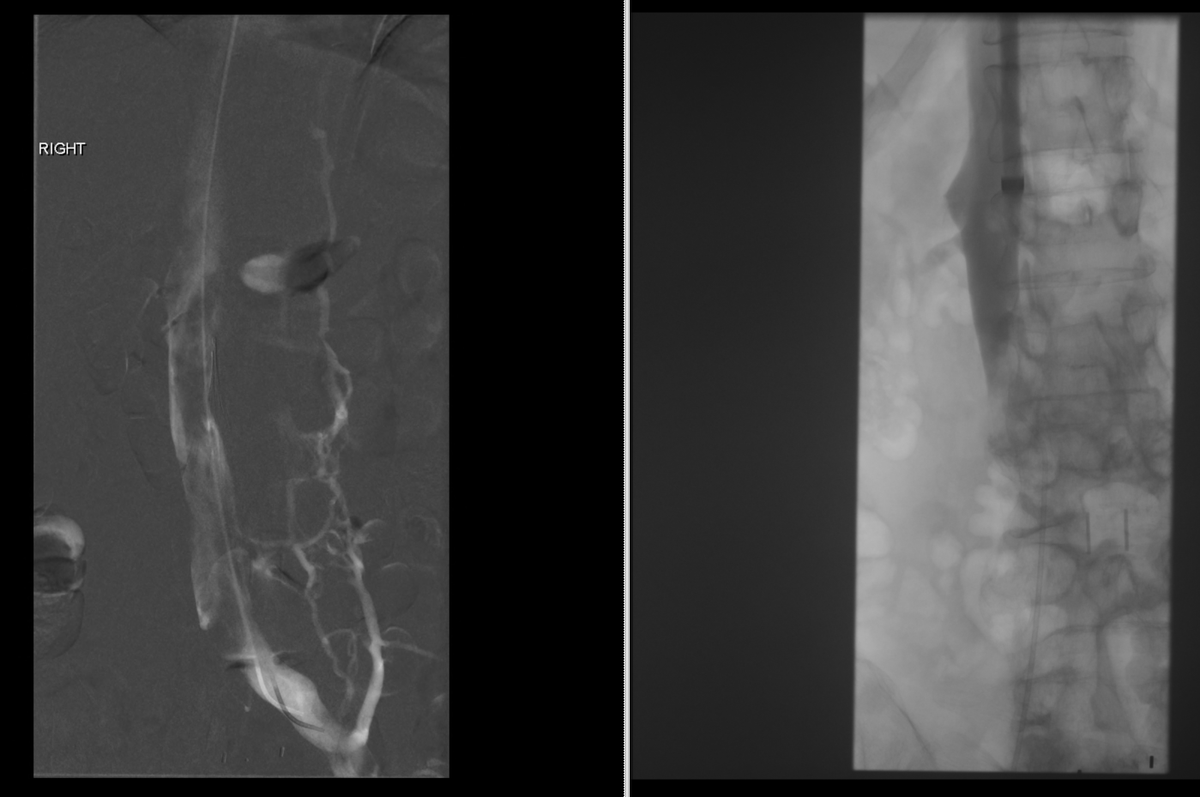

Friendly reminder to get that #IVCFilter out when no longer needed. This patient had acute thrombosis of her IVC and right iliac veins 2.5 years after placement. Clean as a whistle after @BostonPIMedEd #AngioJet thrombectomy and tPA Thrombolysis w #FilterOut. 2 year f/u CT #iRad

1

3

25